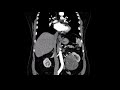

Диагностика нейроэндокринной опухоли желудка включает различные методы, такие как эндоскопия, биопсия и образовательные методы, включая компьютерную томографию (КТ) и магнитно-резонансную томографию (МРТ).